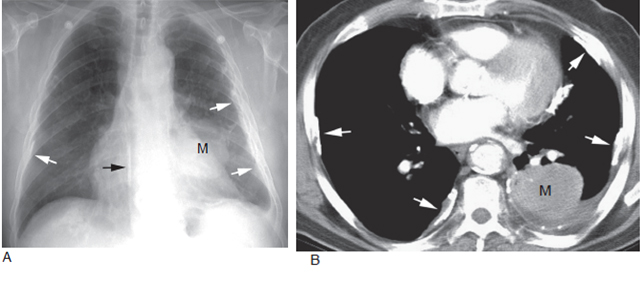

A. 胸片显示左肺肿块(M) 提示肺癌,可见双侧胸膜增厚伴钙化(箭头);B.CT 显示左肺肿块(M) 和双侧局限性胸膜钙化斑(箭头),为石棉肺的典型表现